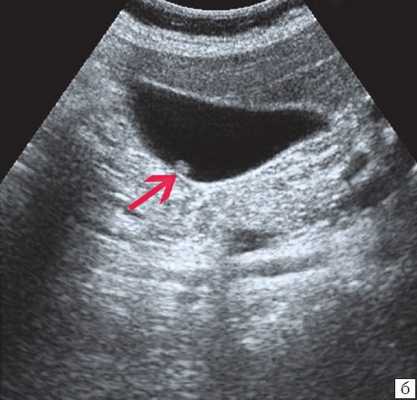

- УЗИ желчного пузыря. Эхогенная картина не слишком специфична и достаточно изменчива. На мониторе можно увидеть изменение структуры, толщины стенок, значительное увеличение объема пузыря. Внутри органа визуализируется скопление желчи, возможно с газовыми пузырьками, неоднородным осадком, хлопьями. В перипузырном пространстве обнаруживается выпот и скопление жидкости.